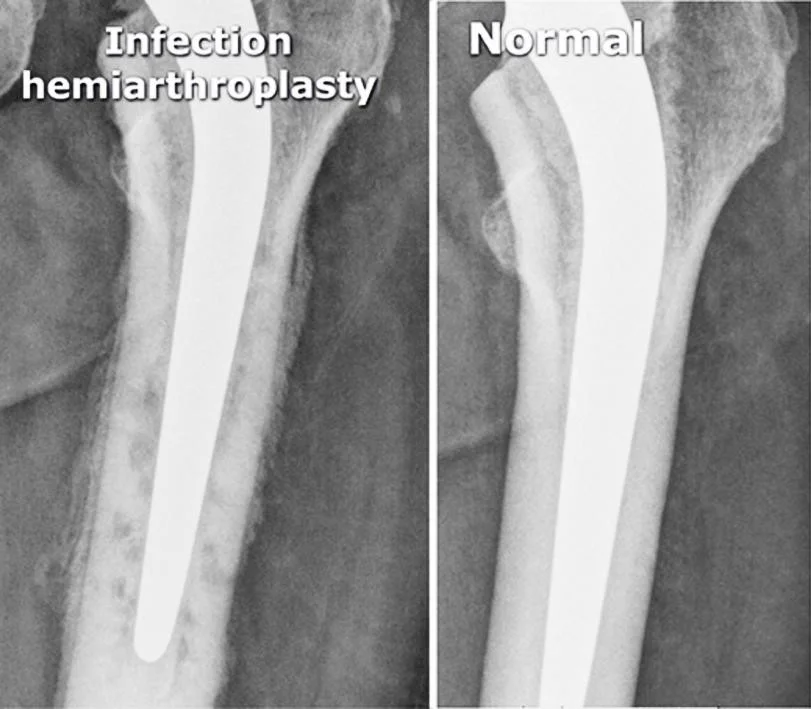

Infected Arthroplasty

- Pain after arthroplasty

- Mild fever

Infection hemiarthroplasty

- vague periprosthetic bone resorption

- periosteal reaction

- cement

Normal

- hemi-arthroplasty